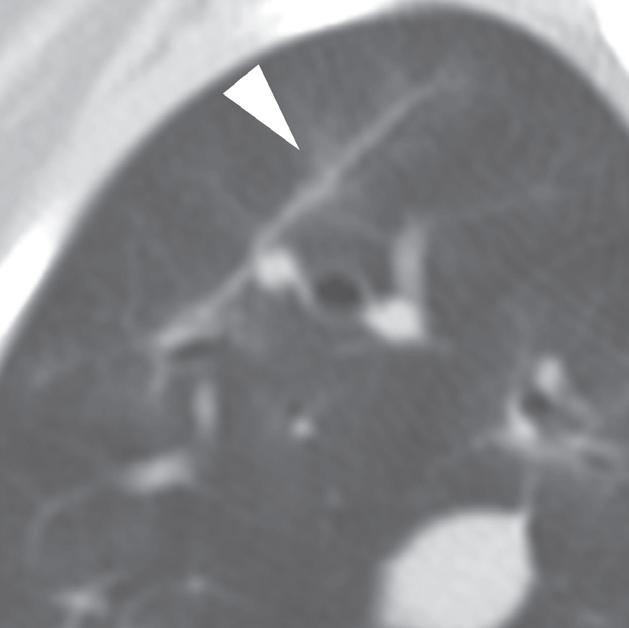

U 6-letniego samca rasy rhodesian ridgeback od 4 dni obserwowano objawy wskazujące na chorobę móżdżku. Stwierdzono słabo odgraniczony, izointensywny w T1 i hiperintensywny w T2 obszar w robaku i lewej półkuli móżdżku (a, b – groty strzałek), któremu nie towarzyszył żaden znaczący efekt masy. Po podaniu kontrastu nie zobrazowano wzmocnienia zmiany. Test immunofluorescencji pośredniej (IFA) wykazał miano zgodne z aktywnym zakażeniem Neospora. Badanie pośmiertne wykonane ok. 3 miesięcy po wstępnym rozpoznaniu potwierdziło martwicze, ziarniniakowe zapalenie móżdżku z pierwotniakami odpowiadającymi Neospora wewnątrz ognisk